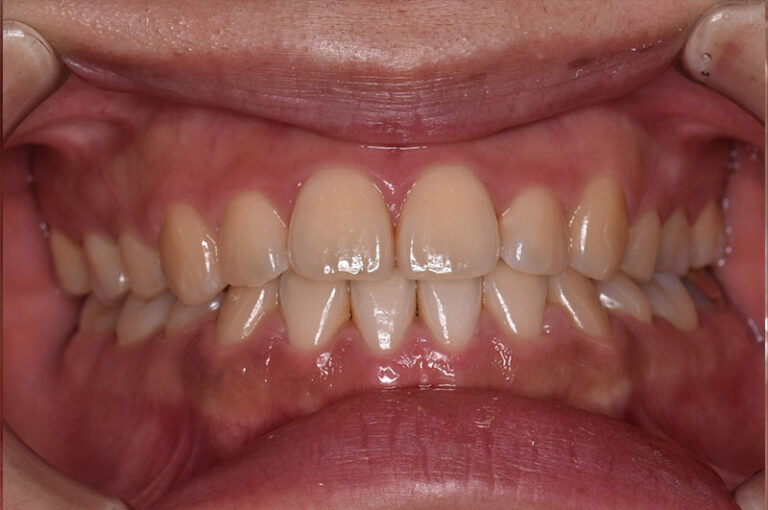

今回は反対咬合に対して、外科手術を行わずに矯正治療のみで改善した成人の症例をご紹介します。

「反対咬合=手術が必要」と思われがちですが、噛み合わせの状態によっては、今回のように矯正治療だけで改善が可能なケースもあります。

治療前後の変化を実際の症例写真でご覧いただくことで、

反対咬合がどのように改善するのかを、イメージしていただければと思います。

症例の概要(手術なし・成人の反対咬合)

術前

術後

| 主訴 | 反対咬合 |

| 初診時年齢 | 24歳 |

| 治療内容・使用した装置 | 頬側ブラケットを用いた永久歯全体の矯正治療、アンカースクリュー |

| 抜歯の有無 | 左右下顎第一小臼歯、左側上顎第二小臼歯抜歯 |

| 治療期間 | 約24ヶ月 |

| 費用 | 総額819,500円(税込) (相談料、検査料、診断料、動的治療費、抜歯費、アンカースクリュー埋入、除去費、保定期間料等含む) |

| 治療に伴うリスク・副作用 | 歯の移動に伴う痛み、上下顎前部の歯根吸収、装置による口内炎、ブラッシング不良によるむし歯、歯周炎 |